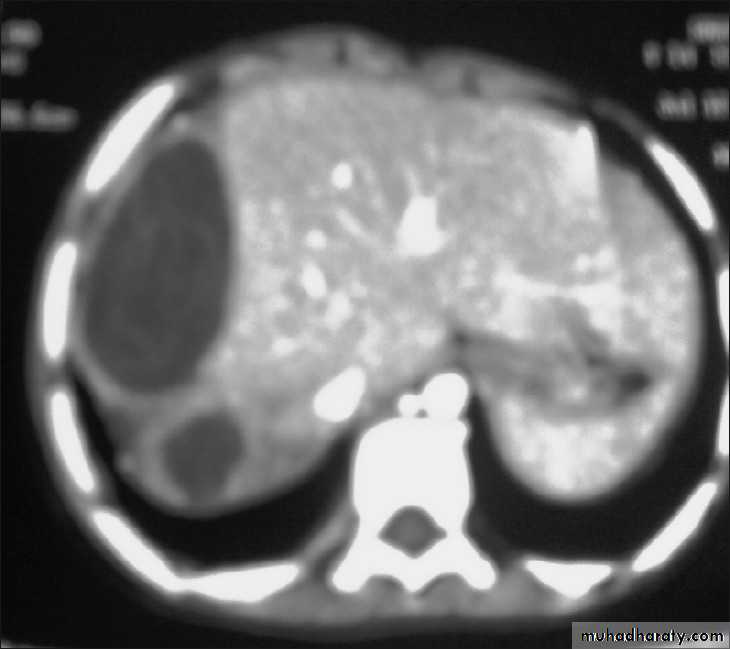

• 1. Disease called Hydatid Cyst, Hydatid disease, Hydatosis.2. No symptoms until the cyst gets large or ruptures.

333. Hepatic Hydatid cyst

• Liver affected in about 65 % of patients• Approximately 70% right lobe is affected.

• Usually no symptoms until the cyst reach 10 cm in diameter : hepatomegaly, nausea, vomiting